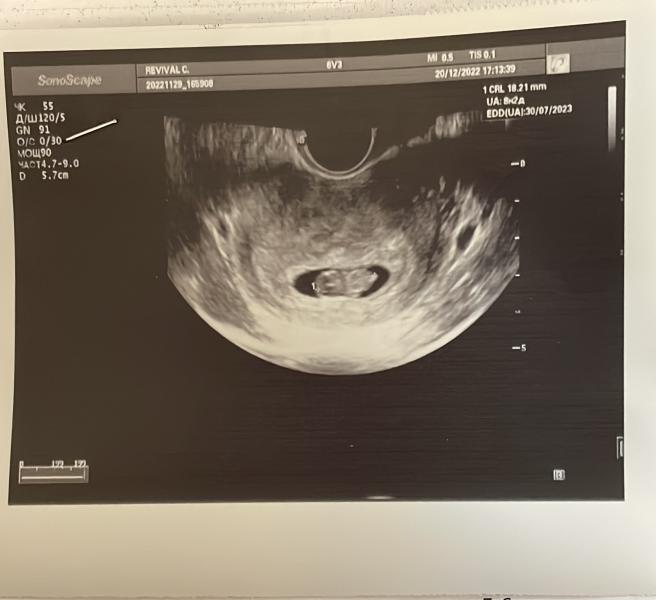

Вот и наше первое фото . Сказали что все хорошо . Надо вставать на учет. А как заставить себя туда пойти ? Врачи там просто «высший уровень» как будто их заставили там работать .. мне кажется в Кремле с такими рожами не сидят . Все важные до ужаса